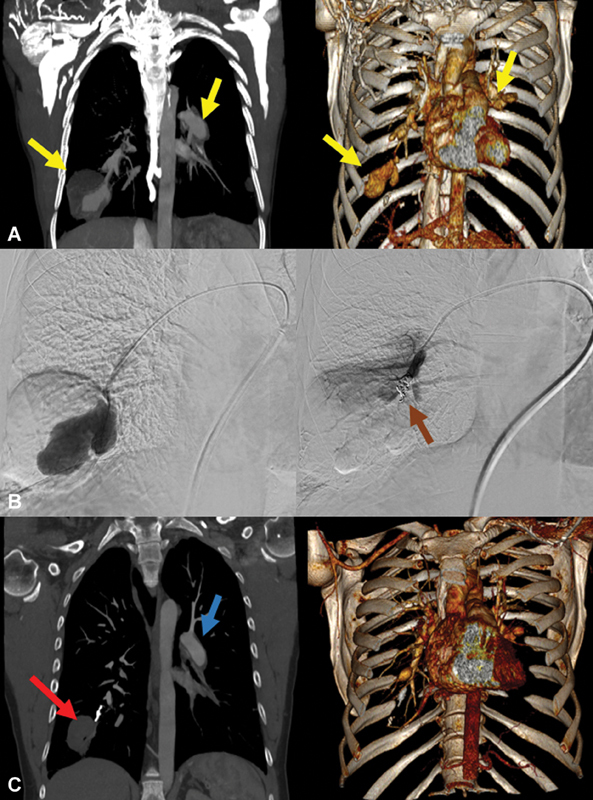

Hughes-Stovin syndrome (HSS) is a rare potentially fatal vasculitis supposedly belonging to the spectrum of Behçet disease without ocular involvement. HSS tends to play by a temporal pattern, starting with thrombosis and followed by formation of pulmonary aneurysms. Since its mortality can reach 25% of cases, early recognition and appropriate therapy represent the major clinical challenges. We describe a rare case of HSS successfully treated via multidisciplinary management by an endovascular approach and immunosuppressive therapy.